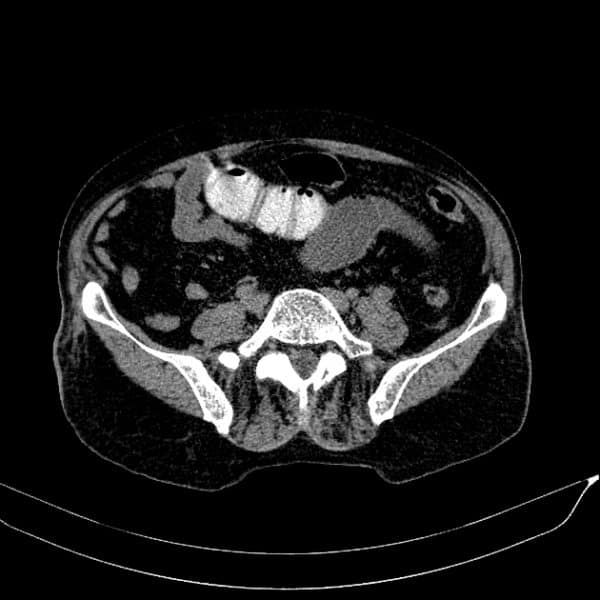

Bezoars

» Thông tin: Nam giới – 80 tuổi.

» Lâm sàng: Đau bụng / Nôn.

# Tắc ruột non do bã thức ăn.